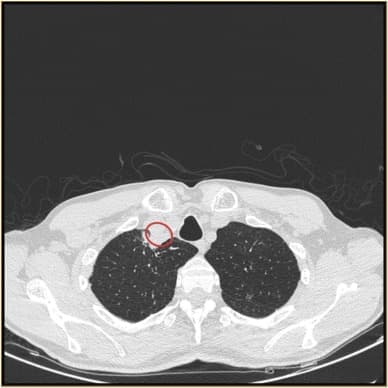

αναφέρεται πως ο ασθενής προσήλθε στο νοσοκομείο με βήχα και βραχνή φωνή, κόπωση και δυσκολία στην κατάποση. Ο αξονικός τομογράφος αποκάλυψε έναν όγκο γεμάτο πύον στην τραχεία του. Οι εργαστηριακές εξετάσεις δε βρήκαν κάποιο βακτήριο και μόνο μία ειδική εξέταση για μύκητες αποκάλυψε την παρουσία μίας ύφας, δηλαδή μίας μακράς, διακλαδισμένης, νηματοειδούς δομής μύκητα.